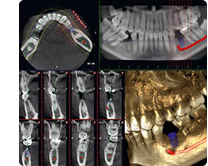

なかの歯科では患者さまに最善の治療を提供するために、設備の最新化への努力をしています。歯科器材の進歩は急速で、適切な判断による設備投資は大きな経費負担を伴いますが、それ以上の治療の効率化・患者さまの治癒率の向上で十分補えると考えております。

なかでも歯科用CTは、通常のX線写真では判断しにくかった歯やあごの状態を立体的にとらえることでより正確な診断を行うことができ、安全かつ確実な診療を行う上で非常に有用です。また、最新のCTは放射線量が非常に少なく、照射範囲が狭くすむため、被曝も少なく安心です。

<使用設備>

- PLANMECA ProMax2D/3D